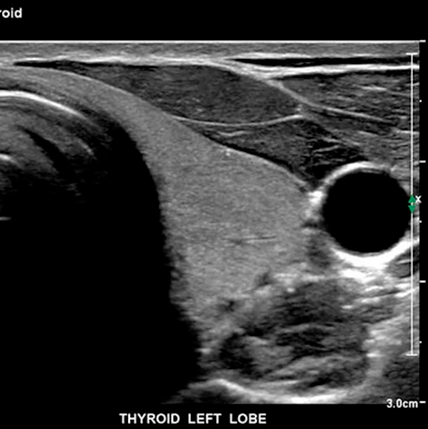

Como ingeniero especializado en el mantenimiento, instalación y reparación de equipos médicos, he tenido la oportunidad de trabajar con una amplia variedad de ecógrafos en centros médicos y clínicas a lo largo de todo Chile. Esta experiencia en terreno me ha permitido identificar los modelos que realmente se han ganado su lugar por su confiabilidad, calidad de imagen, disponibilidad de repuestos y facilidad de operación para los profesionales. Entre ellos destacan equipos como el Philips iU22, conocido por su excepcional resolución y su versatilidad clínica; el GE Vivid E9, altamente valorado en cardiología por su potencia en Doppler y capacidades 4D; y el Siemens X700, una opción sólida en clínicas de mediana y gran escala.

También es importante mencionar modelos orientados a ginecología y obstetricia, como el Voluson S8 de GE, ampliamente utilizado por su rendimiento en imágenes fetales en tiempo real. En cuanto a equipos portátiles, el Philips CX50, Mindray M9 y GE Logiq e han demostrado ser confiables en contextos rurales, domicilios o en pabellones quirúrgicos, donde se necesita movilidad sin perder calidad. Por otro lado, en hospitales de alta complejidad y centros de imagenología avanzada, los equipos de gama alta como el Philips EPIQ 7, Siemens Acuson Sequoia o el Canon Aplio i800 ofrecen un nivel de detalle y procesamiento de imagen que permite un diagnóstico más preciso, incluso en casos complejos.